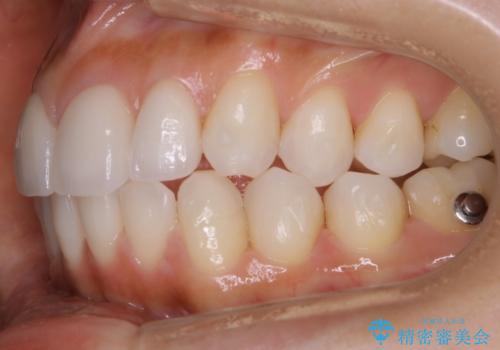

【非抜歯】噛み合わせを整えたい! インビザライン矯正

- 嚙み合わせのズレを主訴にご来院されました。

前歯・奥歯ともにセラミッククラウンで治療されている歯があったため、その歯にあまり影響が出ない範囲内で全体の噛み合わせが良くなるような動きを組み込んで治療を進めることとなりました。